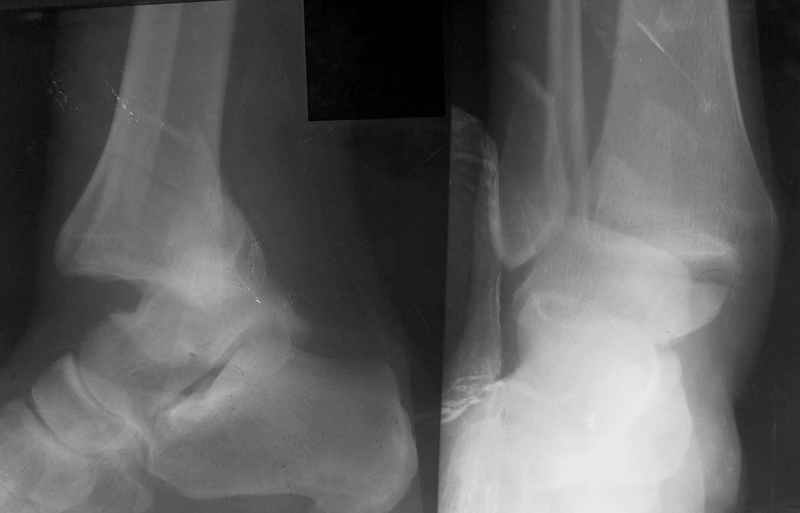

Re: Открытый переломо-вывих стопы.

Алексей Семенистый 20 Апрель 2006, 01:06

>>Это первый мой опыт лечения таких переломов в аппарате Илизарова...

>>ПХО раны, скелетное вытяжение на шине Белера. Через неделю наложен АВФ, устранен вывих стопы...

Никита, а почему через неделю-то???, почему не через две или три? А может надо было сразу вместе с ПХО...